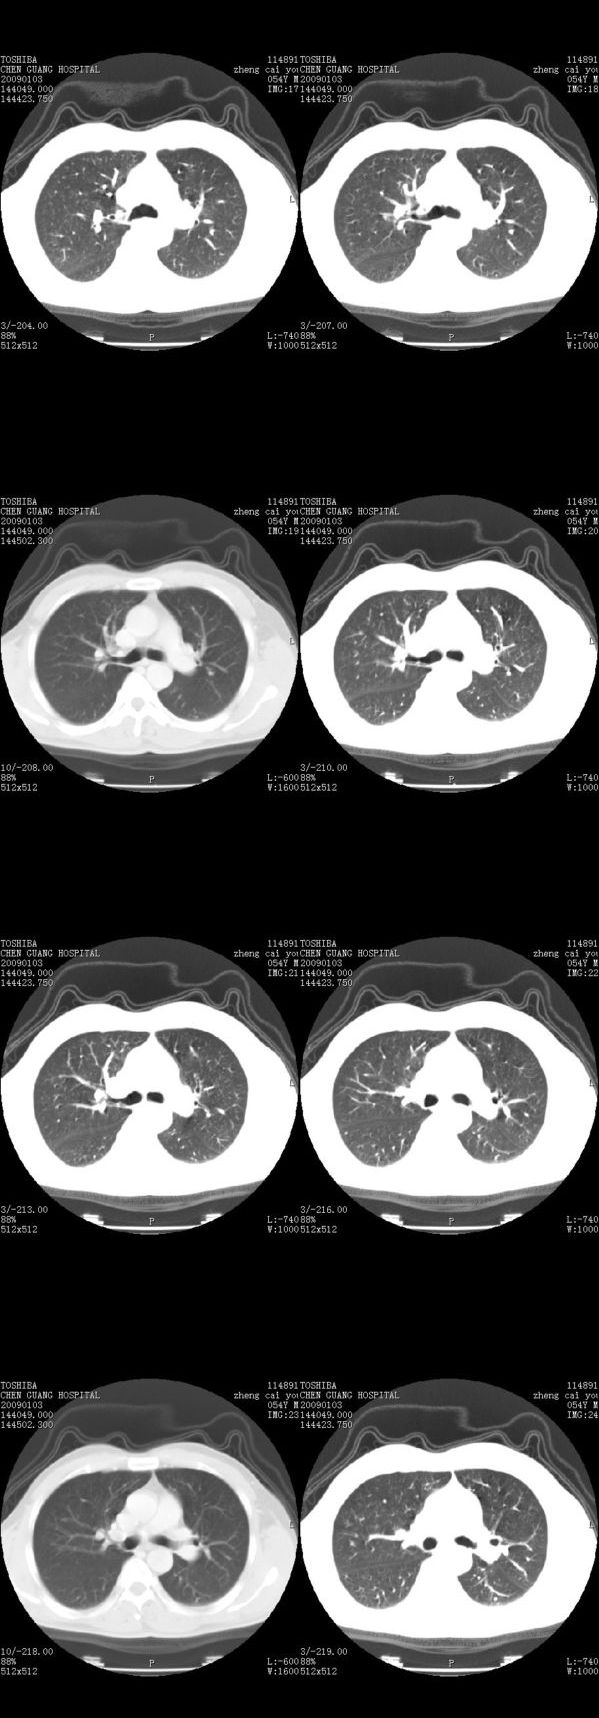

男,54岁,平时有吸烟后咳嗽、咯痰史,因右侧胸部(腋窝下)疼痛来检查平片,见右下肺动脉干起始处处结节,后到同学处做了平扫及增强。请各位老师帮忙看一下,不甚感谢!!!!!

多为血管断面影;建议必要时行ct增强扫描检查。

没有纵膈窗,也没有增强,确实不好说。从连续层面来看像是血管影。不放心做个强化最好了,毕竟是自己最亲的人!!

似乎是血管啊,连续几层都可以看见,希望高手指点迷津!!

肺窗薄扫、常规扫描均未见明确病变;右下肺门圆形与肺血管等密度影,考虑为血管变异;应该要纵隔窗才能进一步明辨。

x线表现与ct扫描相吻合。

主要应该看一下纵隔窗,感觉到右肺门的血管有局限性的扩张,呈结节状,再做个增强ct扫描.

右肺上叶前后段支气管夹角处可见一结节影,图像资料不全,不好下结论。